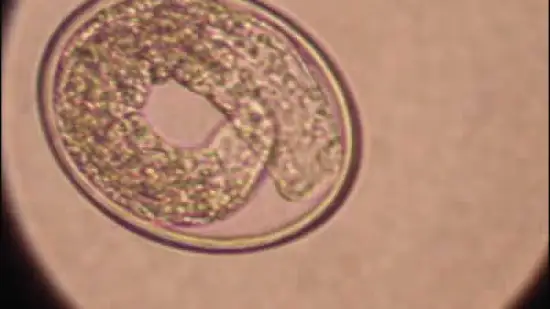

Semana de 02-Ago-2012

Este ovo de parasita pertenece a: